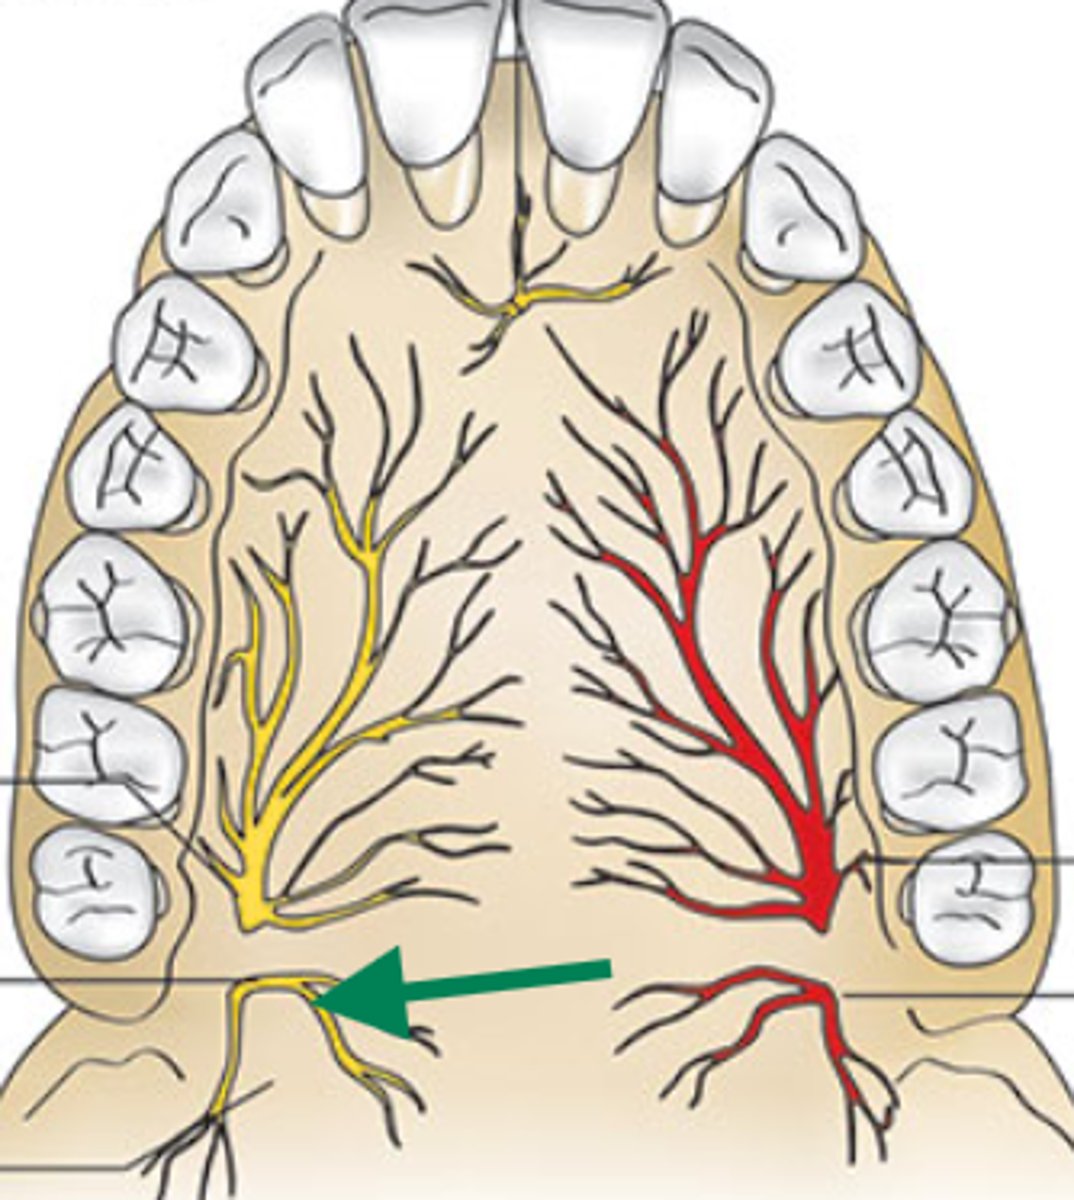

nasopalatine nerve

descending palatine artery

greater palatine nerve

greater palatine artery

greater palatine foramen

lesser palatine nerve

lesser palatine artery

greater and lesser palatine nerve

greater palatine nerve